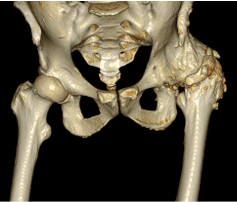

22歳の時(18年前)に左側の股関節に寛骨臼回転骨切り術(RAO)の手術を受けました。

RAO後は骨盤変形が生じているため、手術難易度は格段に上がります。そのため手術対応可能な施設が限られています。

人工股関節手術(THA)の前は覆いかぶさった骨が邪魔をして関節の動きが悪く、椅子に座って立ち上がるのにも苦労していました。